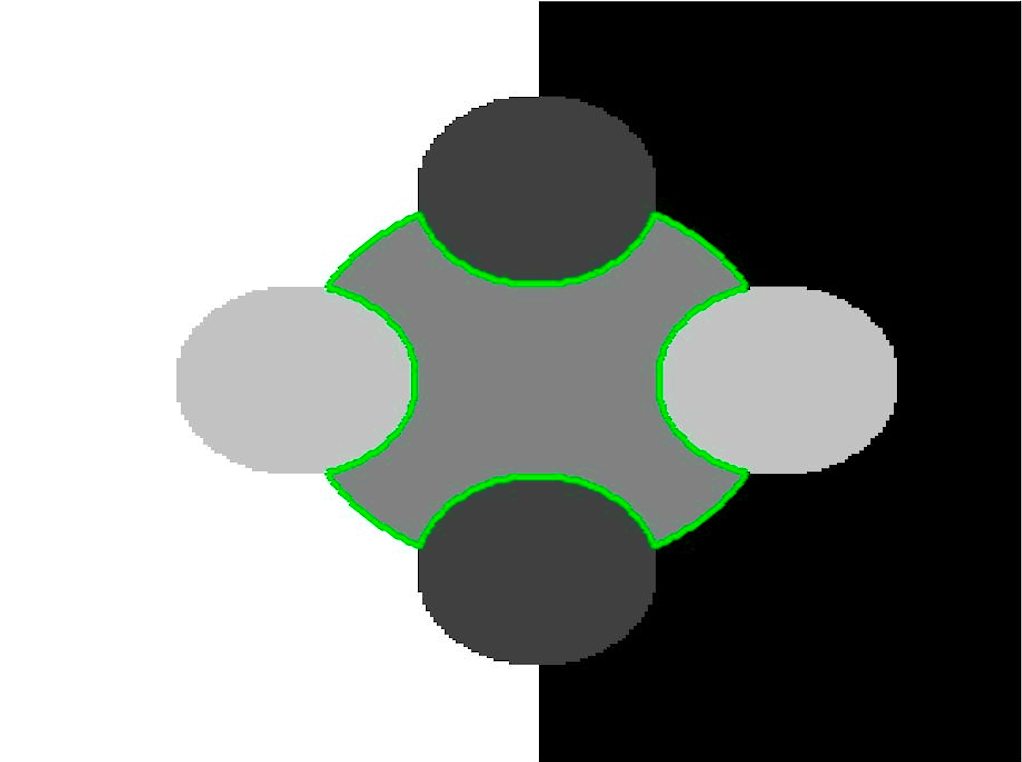

The motivation for this work comes from observing contradictions in using piecewise-constant intensity fitting terms in selective segmentation. Whilst good results are possible with this approach, the exceptional cases lead to severe limitations in practice. This is quite common in medical imaging as demonstrated in Fig. 1, where the target foreground has a low intensity. Given that the corresponding background includes large regions of low intensity, the optimal average intensities for this segmentation problem are and . For cases where , we see that by (1), almost everywhere in the domain . This means that it is very difficult to achieve an adequate result, without an over-reliance on the user input or parameter selection.

| (10) |

where is noise, is the characteristic function of the region , for respectively. The idea of selective segmentation is to incorporate user input to apply constraints that exclude regions classified as foreground, based on their location in the image. We use a distance constraint which penalises the distance from the user input markers. However, a key problem for selective segmentation is that for cases where the optimal intensity values and are similar, the intensity fitting term will become obsolete as the contour evolves. This is illustrated in Fig. 3. The purpose of our approach is to construct a model that is based on assumptions that are consistent with the observed image and any homogeneous target region of interest. A common approach in selective segmentation is to discriminate between objects of a similar intensity Rada:13 ; Geo ; CDSS . However, the fitting terms in previous formulations Klodt:13 ; Rada:13 ; Geo ; CDSS aren’t applicable in many cases as there are contradictions in the formulation in this context. We will address this in detail in the following section.

In this section we introduce the proposed data fitting term for selective segmentation. We consider objects that are approximately homogeneous in the target region. Intrinsically, it is then assumed that the region , provided by the user, is likely to provide a reasonable approximation of the optimal value and therefore an appropriate foreground fitting function, , is given by CV (2). For this reason, it makes sense to retain this term in the proposed approach. The contradiction is in how the background fitting function is defined. Considering piecewise-constant assumptions of the image, and many of the related approaches, the background is expected to be defined by a single constant value, . If then everywhere, and therefore the fitting term can’t accurately separate background regions from the foreground. It is not practical to rely on to overcome this difficulty as it will produce an over-dependence on the choice of and . This is prohibitive in practice. An alternative function must therefore be defined which is compatible with and . Here, we define a new data fitting term that penalises background objects in such a way that avoids these problems by allowing intensity variation above and below the value . In order to design a new functional, we first look at the original CV background fitting function

We define the proposed data fitting functional as follows:

for and as defined in (33). This is consistent with respect to the intensities of the observed object and the concept of selective segmentation. In Fig. 3 we see the difference between CV and the proposed fitting terms for given user input on a CT image. For the CT image, the CV fitting terms are near 0 within the target region. This is despite there being a distinct homogeneous area with good contrast on the boundary. This illustrates the problem we are aiming to overcome. With the proposed fitting term this phenomenon should be avoided in cases like this. By defining as in (33) there is no contradiction if the foreground and background intensities of the target region are similar.